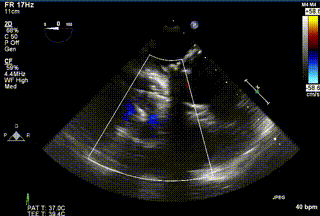

2021年12月24日,復(fù)旦大學(xué)附屬中山醫(yī)院葛均波院士團(tuán)隊(duì)成功應(yīng)用LuX-Valve Plus為一例極重度三尖瓣反流(TR)合并房顫、房缺的患者完成了經(jīng)血管三尖瓣置換術(shù),這是在前基礎(chǔ)上,本周完成的第三例經(jīng)血管三尖瓣置換手術(shù),葛均波院士、周達(dá)新教授等與心外科魏來教授、賴顥教授,心超室的潘翠珍教授、李偉教授及麻醉科的郭克芳教授共同完成了本周手術(shù),均獲得圓滿成功!患者術(shù)后超聲顯示無TR,臨床癥狀明顯改善。本周手術(shù)的成功也為LuX-Valve Plus救治性臨床研究添上了濃墨重彩的一筆。

三例患者入院后,葛均波院士團(tuán)隊(duì)周達(dá)新教授、潘文志教授、張?jiān)床┦俊㈥惿┦考靶某业呐舜湔浣淌?、李偉教?/strong>對(duì)患者的情況進(jìn)行詳細(xì)評(píng)估和討論,最終決定為三例患者選擇LuX-Valve Plus40mm、50mm和50mm型號(hào)的瓣膜進(jìn)行手術(shù)治療。手術(shù)后即刻拔除氣管插管,術(shù)后患者三尖瓣反流癥狀得到顯著改善,復(fù)查心超結(jié)果顯示人工三尖瓣瓣膜支架固定穩(wěn)定,瓣葉關(guān)閉形態(tài)未見異常,未見明顯反流。